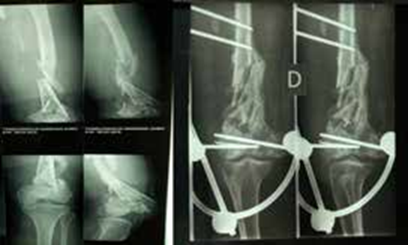

Seize patients avec 16 fractures ouvertes du fémur distal étaient retenus dont 11 hommes et 5 femmes, d’âge moyen de 35,5 ans (extrêmes : 18 et 72 ans). Les résultats pertinents sont exposés dans les Tableaux 1, 2, 3 et 4 et illustrés par les Figures 1, 2 et 3.

Avant l’an 2018, les implants utilisés étaient les broches, la plaque condylienne ou le fixateur externe. Avec ces implants, les résultats du traitement n’étaient pas assez satisfaisants. Ainsi, l’idée était de choisir en première intention les Vis-plaque condyliennes DCS et les LCP. Les résultats étaient alors très satisfaisants chez les 6 patients opérés. Plusieurs auteurs avaient également obtenu des résultats satisfaisants avec les implants du système AO [11, 12, 17]. Dans cette étude, faute de moyens financiers, les 10 premiers patients ne pouvaient pas acheter les implants AO. Cette particularité exceptionnelle expliquait pourquoi les résultats de cette étude étaient moins satisfaisants avant l’an 2018. En outre, il importe de souligner l’efficacité des implants du système AO dans la réduction peropératoire des fractures. Cette efficacité était également confirmée par les résultats de cette étude. Cependant, les complications à type de raideur du genou existent [18]. Dans cette étude, 4 patientsavaientcommencé leurrééducationaprès le premier mois du post-opératoire. Quatre autres avaient commencé la rééducation durant la première semaine du post-opératoire. Les résultats de la rééducation des 2 cas de raideur du genou étaient proches de ceux de Manou et al. [19]. Pour une raideur légère du genou l’attitude était de tenter une récupération par la rééducation [7].